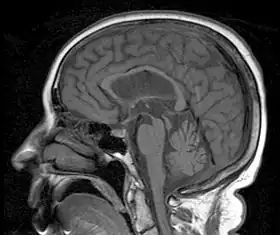

| MRI demonstrating the hummingbird sign of supranuclear palsy due to atrophy of the midbrain | |

Magnetic resonance imaging (MRI) is often used to diagnose PSP. MRI may show atrophy in the midbrain with preservation of the pons giving a "hummingbird" sign.[26]